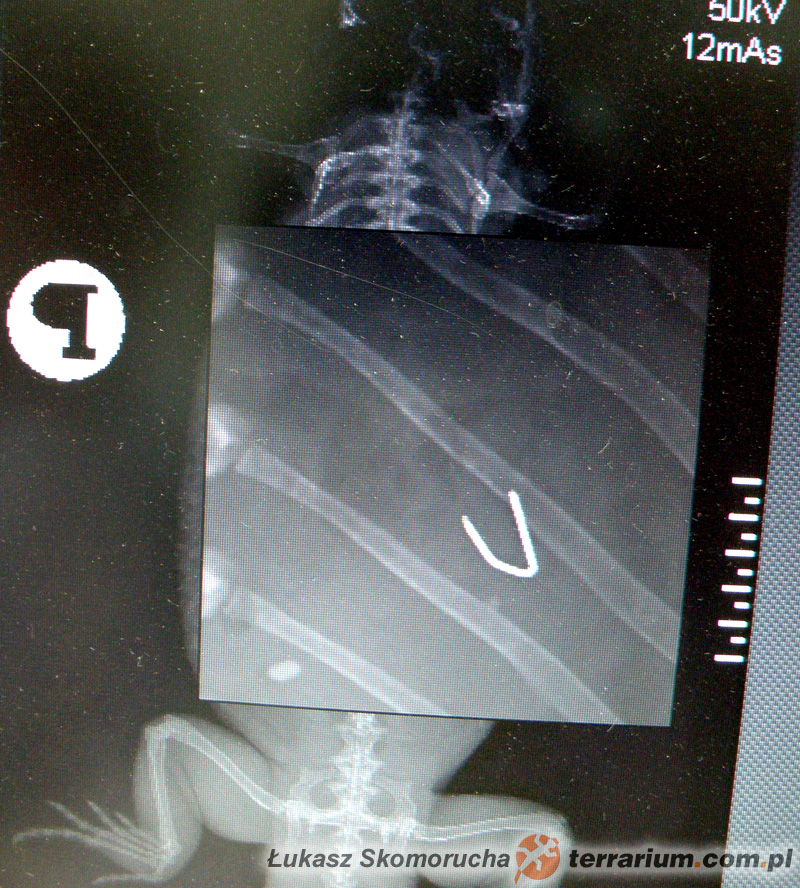

- CIAŁA OBCE podzielić można na dwie kategorie – cieniujące i niecieniujące w obrazie RTG. W przypadku tych pierwszych nie ma najmniejszego problemu ze stwierdzeniem ich obecności np. w przewodzie pokarmowym, w którym mogą wywoływać niedrożność. Doskonale cieniują, czyli pozostawiają wyraźny obraz na kliszy rentgenowskiej, między innymi monety, śruby i inne metalowe przedmioty, kamienie, piasek. Ciała obce niecieniujące są uformowane z tworzyw słabo lub w ogóle nie pochłaniających promieniowania rentgenowskiego – nie są bezpośrednio widoczne na zdjęciu, jednak zachodzące w organizmie procesy mogą niejako pobocznie wykazać ich obecność. Przyjmijmy na przykład, iż legwan zielony podczas spaceru po mieszkaniu połknie torebkę foliową (przypadek autentyczny!). Zakładamy, iż właściciel legwana nie zauważy samego zdarzenia, a przez kilka kolejnych dni nie spostrzeże braku rzeczonej torby. Zaniepokoi go dopiero fakt, iż jaszczurce zmniejszy się apetyt, przez dłuższy czas nie wydali kału, a obrys brzucha zacznie się wolniej lub szybciej powiększać. Lekarz, podejrzewając niedrożność jelit (zaczopowanie), wykona kontrolne zdjęcie RTG. Problem w tym, że sama foliowka będzie bardzo słabo widoczna w obrazie RTG. Widoczny będzie natomiast ogólny obraz przewodu pokarmowego, którego dystalna (znajdująca się za zatorem, bliżej kloaki) część będzie pusta, natomiast fragment przed zatorem wypełniony będzie tworzącymi się masami kałowymi, które – z racji przeszkody – nie będą mogły przedostać się dalej. Dodatkowo często dochodzi do nagromadzenia się gazów fermentacyjnych (wzdęć), a te, jako bardziej przepuszczalne dla promieniowania niż tkanki organizmu, będą doskonale widoczne jako przestrzenie przejaśnień (czarne plamy). W ostateczności, w przypadkach trudnych do interpretacji, można wykorzystać specjalne środki kontrastujące. Doskonale cieniują, co umożliwia obserwację ich pasażu (przechodzenia) przez kolejne odcinki układu pokarmowego. Oczywistym jest, iż tuż przed zatorem cała ich masa ulegnie zatrzymaniu i nagromadzeniu, a lekarz uzyska po pierwsze potwierdzenie podejrzenia obecności ciała obcego, po drugie – pozna dokładną jego lokalizację. Ciała obce, które są słabo lub wcale niecieniujące, to m.in. drewno (w tym stosowane jako podłoże kostki bukowe), tkaniny, niektóre rodzaje gum i tworzyw sztucznych, pestki itp.